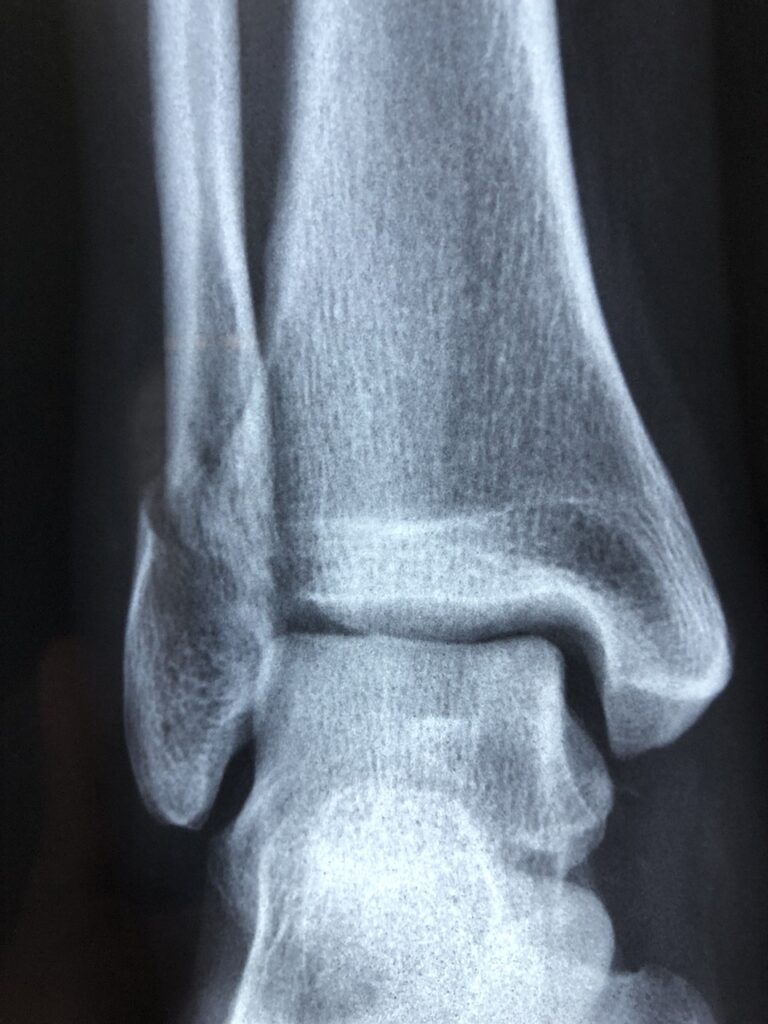

野球をプレイする際、足首の捻挫は非常に一般的な怪我の一つです。特に、走塁や守備の際に急に方向を変えたり、足を踏み外したりすることで、足首に大きな負担がかかります。捻挫は軽いものから重いものまであり、軽いものであれば数日で回復することもありますが、重度の場合は長期間のリハビリが必要となることもあります。